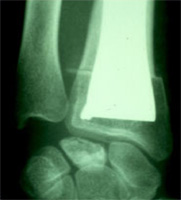

Le traitement d’un cal vicieux du poignet consiste le plus souvent en une ostéotomie, c’est-à-dire que l’on coupe le radius au niveau de la déformation, qu’on remet l’os en place dans un alignement normal et que l’on fixe cet os par du matériel qui est soit une plaque, soit une série de broches.Suivant la solidité du système, on met un plâtre pour cinq semaines ou on permet une mobilisation douce dès la première semaine. Dès que la consolidation est affirmée par les radios, on peut entreprendre une rééducation pour regagner le maximum de mouvements.Parfois, les troubles ne portent que sur la prono-supination et l’intervention porte alors seulement sur l’ulna : raccourcissement par résection (opération de Darrach ou vissage des deux os, en enlevant un cylindre d’os pour permettre le mouvement (intervention de Sauvé-Kapandji).

![]() |

|

Ostéotomie avec ostéosynthèse |

Intervention de Sauvé-Kapandji |